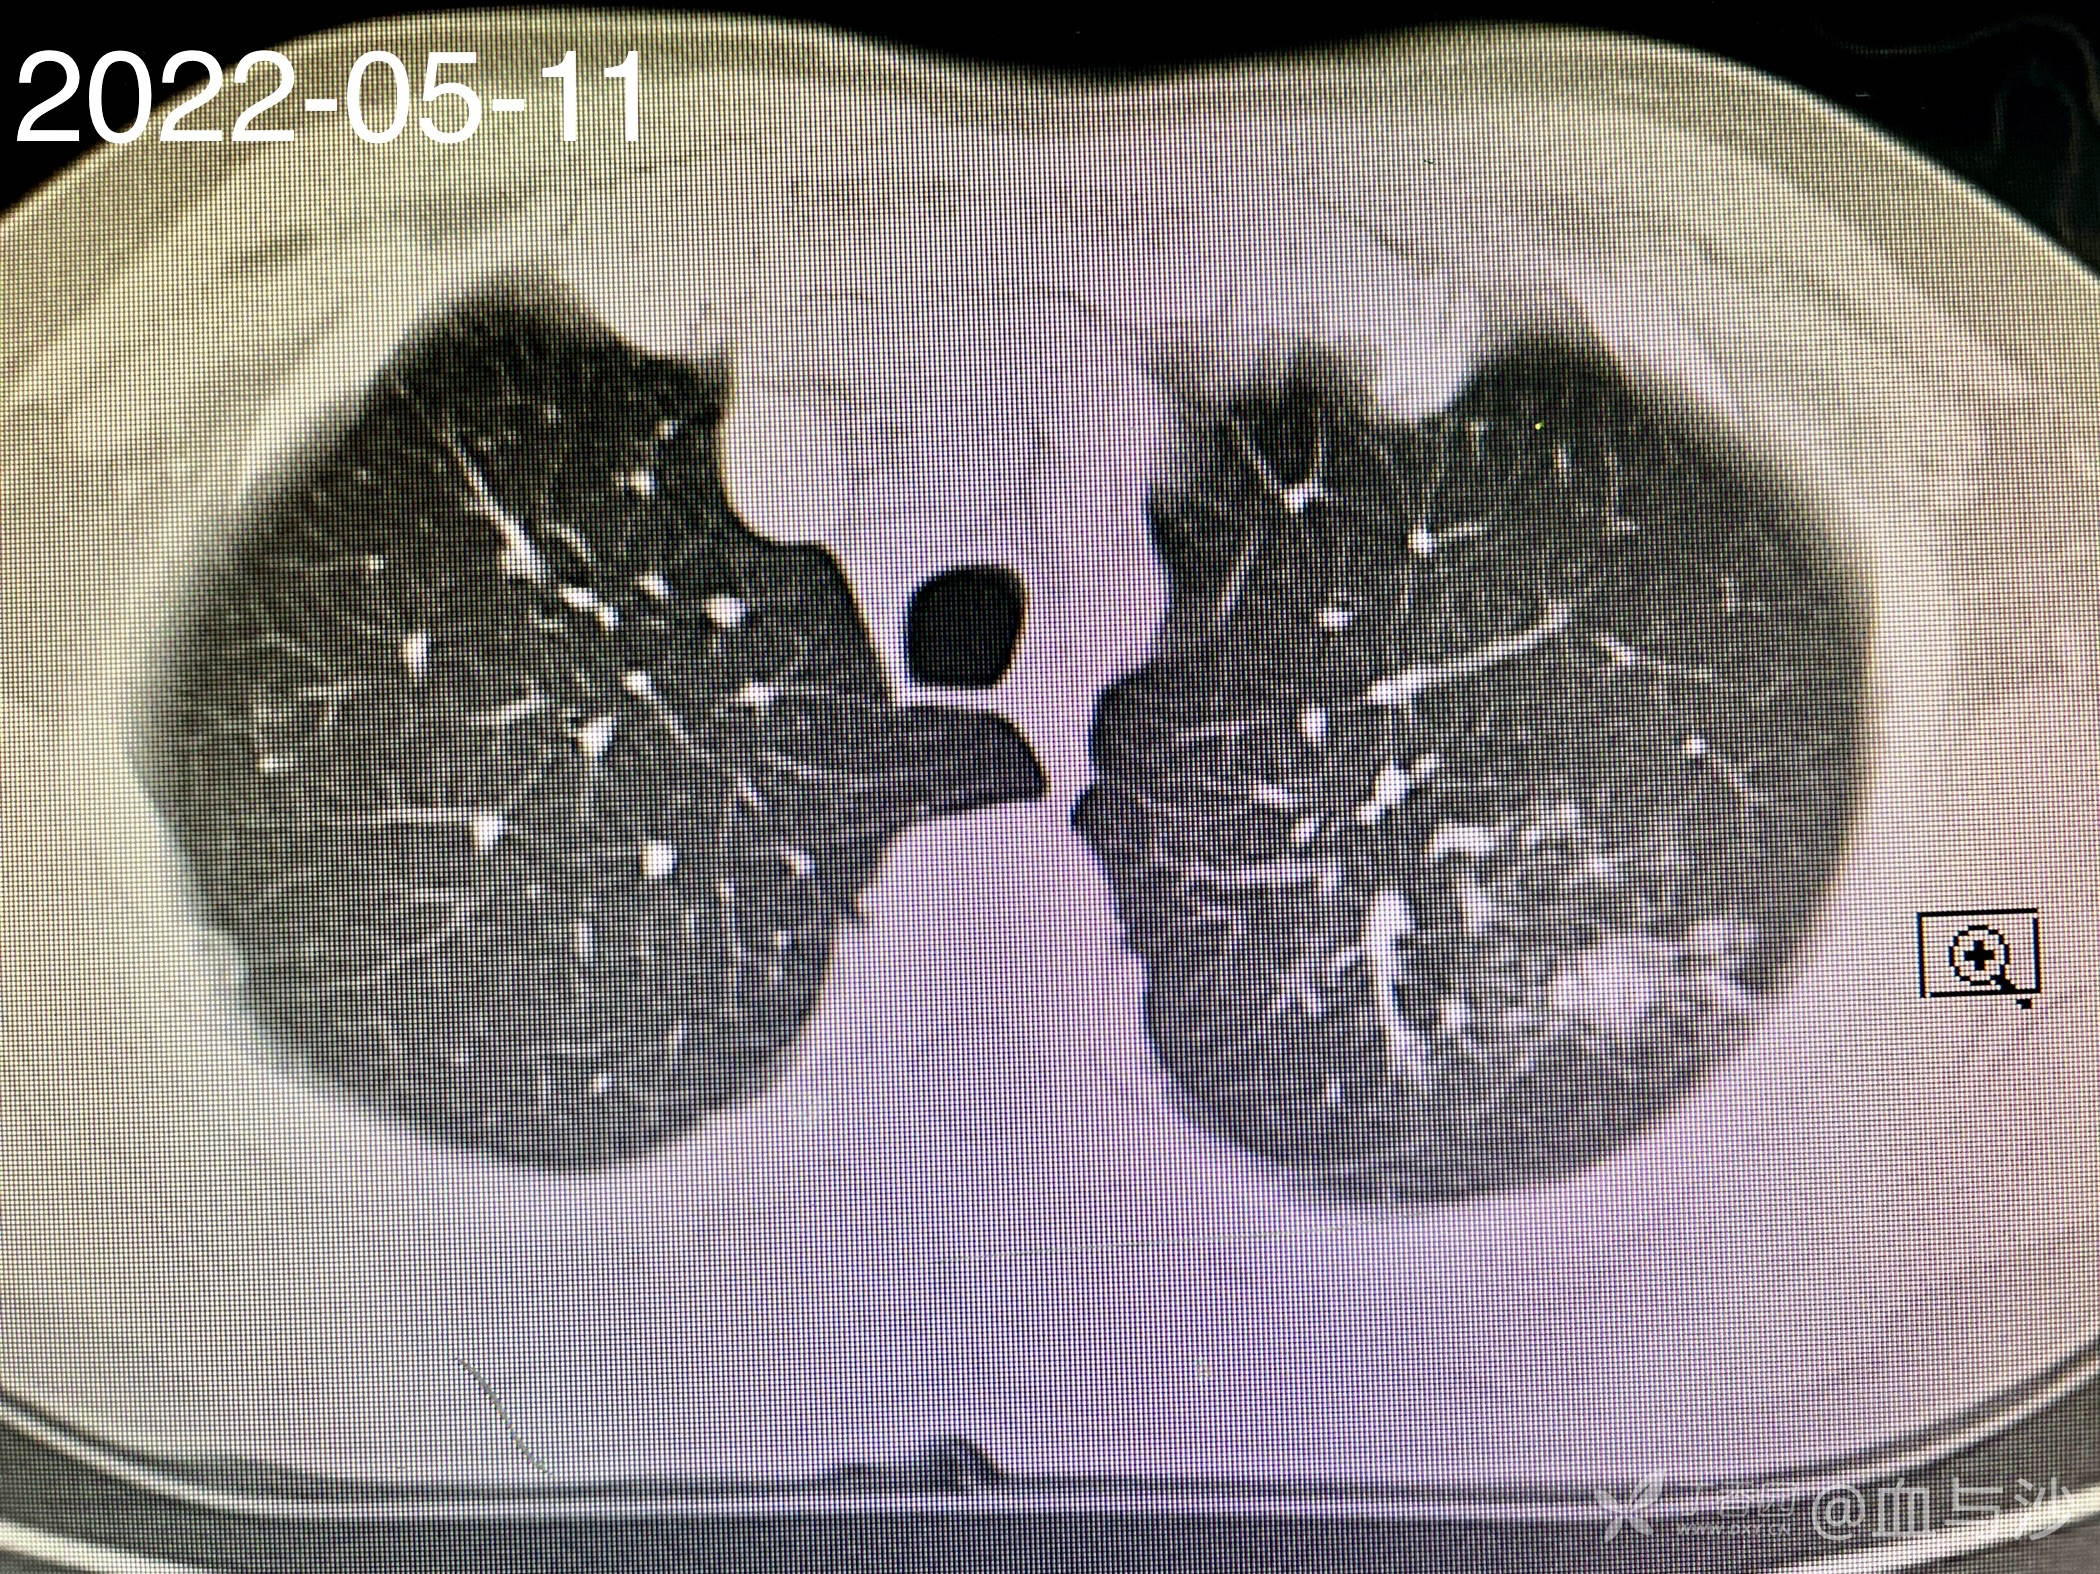

病人女,60岁,去年4月底因咳嗽发热入院,诊断支气管扩张伴感染(结核各项检查阴性,病人平时也无潮热盗汗),予抗感染对症处理。当时CT片左肺上叶有一磨玻璃样影。今年5月病人再次咳嗽发热入院,续按照支扩伴感染处理,但CT显示去年的磨玻璃影成了一约1.5cm的实性结节。

以下是今年5月的CT影像: